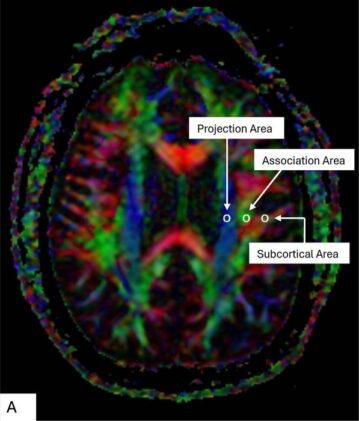

The team focused on the glymphatic system. It’s the network of fluid-filled channels that carries waste out of the brain, something like housekeeping for neurons. The idea sounds simple. Measure how well water moves through the perivascular space using diffusion tensor imaging along those channels, a technique called DTI-ALPS, and compare fighters who show cognitive problems with those who don’t. It should give a snapshot of how the system responds to years of hits.

The data came from 280 fighters enrolled in the Professional Athletes Brain Health Study, a long-running project that tracks about 900 participants. Ninety-five of them were already cognitively impaired at baseline. There were also twenty healthy controls who provided something like a reference point. Everyone went through MRI scans so the researchers could compute an ALPS index, a number that reflects how efficiently the glymphatic system is moving fluid.